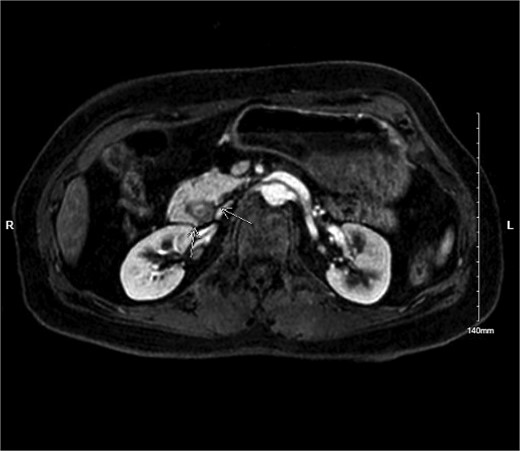

Physical exam was significant for epigastric and bilateral upper quadrant abdominal tenderness without guarding. Notably, her urinalysis was positive for ketones. Abdominal CT with intravenous contrast ordered in the emergency department revealed a near complete annular pancreas at the level of the first portion of the duodenum with concurrent gastric and duodenal bulb distension with no evidence of pancreatitis (See Fig. 1). Nasogastric tube decompression and antiemetic therapy were initiated, and the patient underwent magnetic resonance cholangiopancreatography (MRCP), which revealed severe duodenal narrowing at the second portion with circumferential encasement of the pancreas (See Fig. 2).

Abdominal CT with IV contrast showing fluid distension of the stomach and duodenal bulb with encirclement of pancreatic tissue around the first portion of the duodenum.